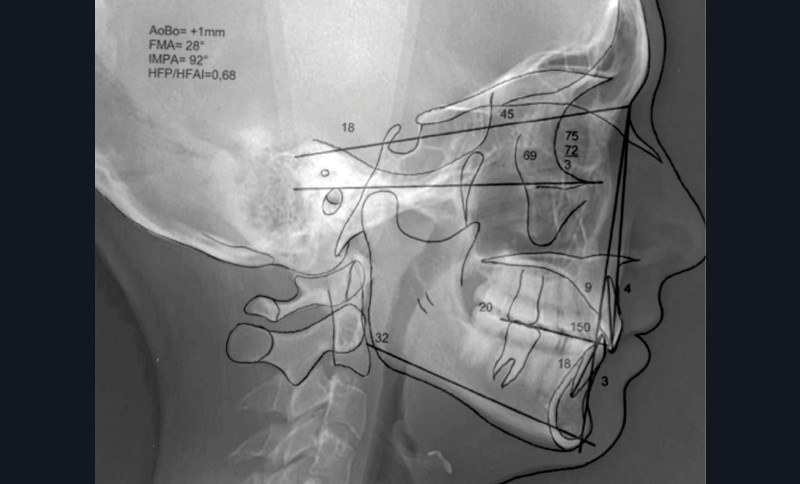

La radiographie panoramique et la téléradiographie de profil objectivent (fig. 3 et 4) :

- une classe I squelettique (angle ANB = 3°) ;

- une normodivergence (angle GoGn/SN = 32°)…